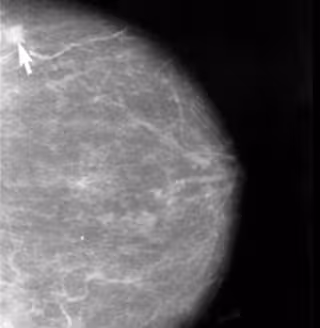

Un equipo de especialistas de la Clínica Universidad de Navarra desarrolla un ensayo clínico para tratar el cáncer de mama triple negativo con el fármaco Vismodegib, asociado a quimioterapia convencional.

El objetivo del estudio multicéntrico se centra en probar la eficacia de este tratamiento en un total de 40 pacientes, con el que los especialistas pretenden ampliar el conocimiento de una vía de señalización tumoral que está alterada en aproximadamente en la mitad de los tumores de mama triple negativos.

Dentro del amplio abanico de subtipos de cáncer de mama, aquellos con triple negativo (TN) constituyen el 15%. "Las recaídas de la enfermedad en los tres primeros años son habituales, empeorando de forma considerable el pronóstico una vez que las metástasis han hecho su aparición", ha señalado.